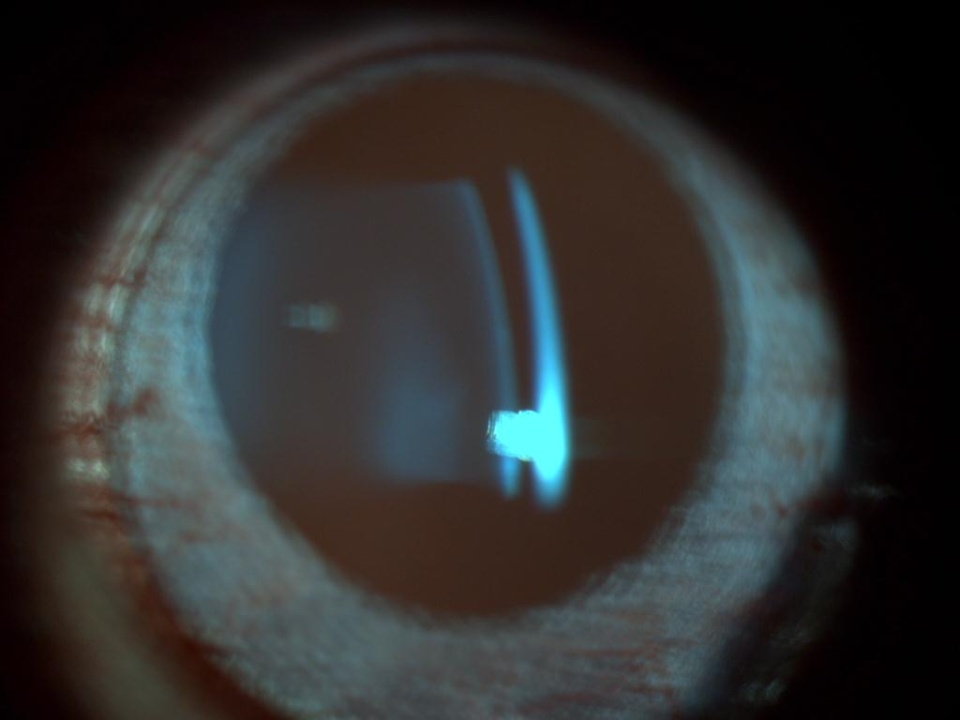

1030_154.jpg